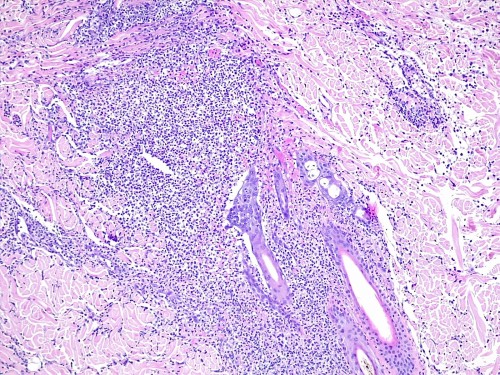

– les biopsies cutanées (LAPVSO) concluent à de sévères lésions de dermohypodermite neutrophilique avec furonculose et lésions hypodermiques ponctuelles de vascularite leucocytoclasique (Photos 4 à 9)

Examen histopathologique montrant un épiderme intact ou sévèrement ulcéré. Dans le derme, on observe un œdème superficiel ainsi que de multiples foyers inflammatoires non encapsulés, souvent à point de départ folliculaire ou périfolliculaire, pouvant fusionner, rompre les follicules pileux et s’étendre dans l’ensemble du derme voire gagner l’hypoderme. Ces foyers sont caractérisés par l’accumulation de granulocytes neutrophiles qui semblent altérés et qui dissèquent les fibres de collagène autour du follicule pileux ainsi que la paroi folliculaire et la lumière folliculaire. De nombreuses plages inflammatoires contiennent des tiges pilaires nues. L’infiltrat peut s’étendre dans l’hypoderme, mais ce dernier est surtout caractérisé par un épaississement des septa conjonctifs interlobulaires du tissu adipeux avec œdème, accumulation d’un matériel fibrinoïde, dilatation vasculaires des vaisseaux lymphatiques et des structures vasculaires de petit calibre, les vaisseaux lymphatiques étant encombrés d’un matériel inflammatoire fibrino-leucocytaire. Il peut exister des images focales de vascularite leucocytoclasique au sein de l’hypoderme.